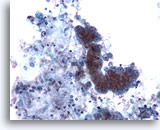

Figure 109

Bronchial wash

A cluster of adenocarcinoma is admixed with respiratory macrophages.

20x